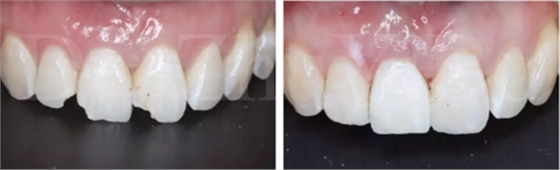

4.2.5 雙區(qū)植骨,戴牙(圖14,圖15)。

圖16 即刻修復(fù)后,患者恢復(fù)了美觀